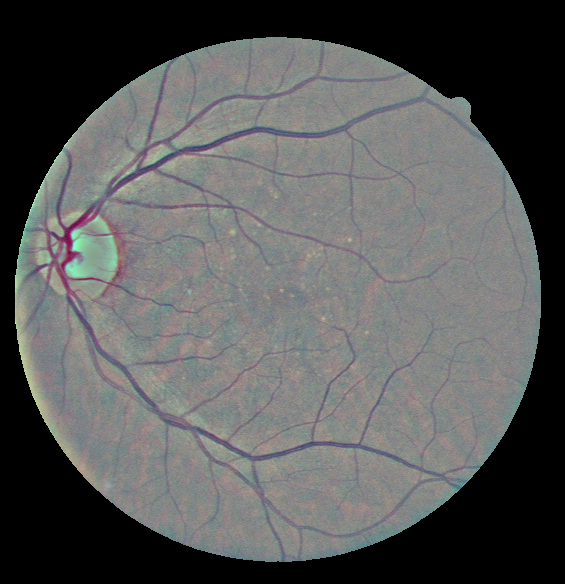

In Figure 4, an example of a retinography before and after applying the preprocessing method is provided, along with the density histograms of vessel pixels and background pixels for each image. The histograms have been computed from the images converted to grayscale.

It can be seen at first glance that the enhanced image, i.e. the one that has been preprocessed, has a greater contrast between the vessels and the background and it presents a more uniform illumination. This enhancement can also be seen in the histograms of the images.